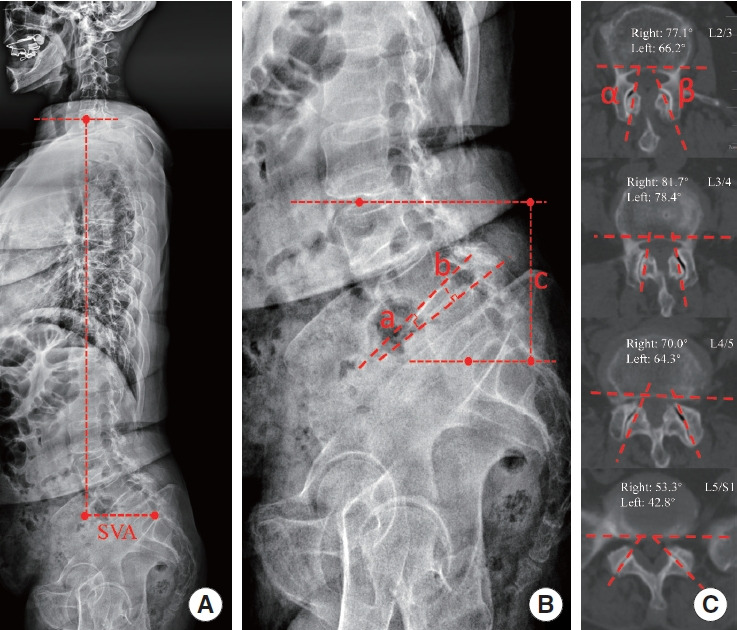

Methods: A total of 40 patients with L3-5 dLDS (mean age, 64.1 years) and 106 patients with L4-5 single-level LDS (sLDS; mean age, 63.5 years) were included. Besides, 100 age-matched healthy participants were recruited as the control group. Facet joint angles at each level from L2-3 to L5-S1 were measured on axial computed tomogrpahy images. Slippage and spinopelvic sagittal parameters were measured using lateral full-spine x-rays.

Results: Both dLDS and sLDS groups had significantly larger facet joint angles from L2-3 to L5-S1 than those in the control group, except for left L5-S1. In patients with spondylolisthesis, the facet joint angles at the L2-3 and L3-4 levels in the dLDS group were significantly greater than those in the sLDS group, while the angles at the L4-5 and L5-S1 levels showed no significant differences. In contrast to the sLDS group, the dLDS group had significantly greater pelvic tilt, sagittal vertical axis, L3 slope, and L4 slope, as well as smaller sacral slope, lumbar lordosis, L3-4 disc height, L4-5 disc height, L4-5 slippage angle, and L3-S1 height. Age and dLDS were identified as independent factors influencing the changes in the L3-4 facet joint angles between the 2 LDS groups.